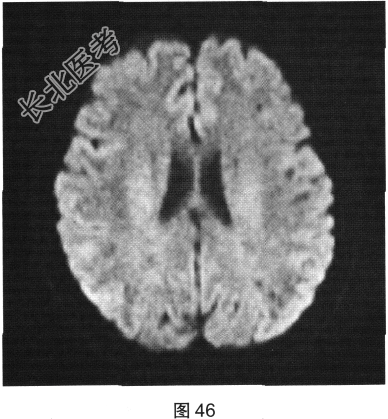

- 多项选择题2.[提示]患者行FLAIR、DWI及增强扫描,见图45~图54。该患者MRI影像的主要阳性表现有( )

C、双侧放射冠及半卵圆中心多发条状、圆形及卵圆形异常信号灶

D、病灶呈长T1、长T2信号,FLAIR为低信号,DWI为高信号,ADC为低信号

E、病灶呈长T1、长T2信号,FLAIR为低信号,DWI为低信号,ADC为高信号